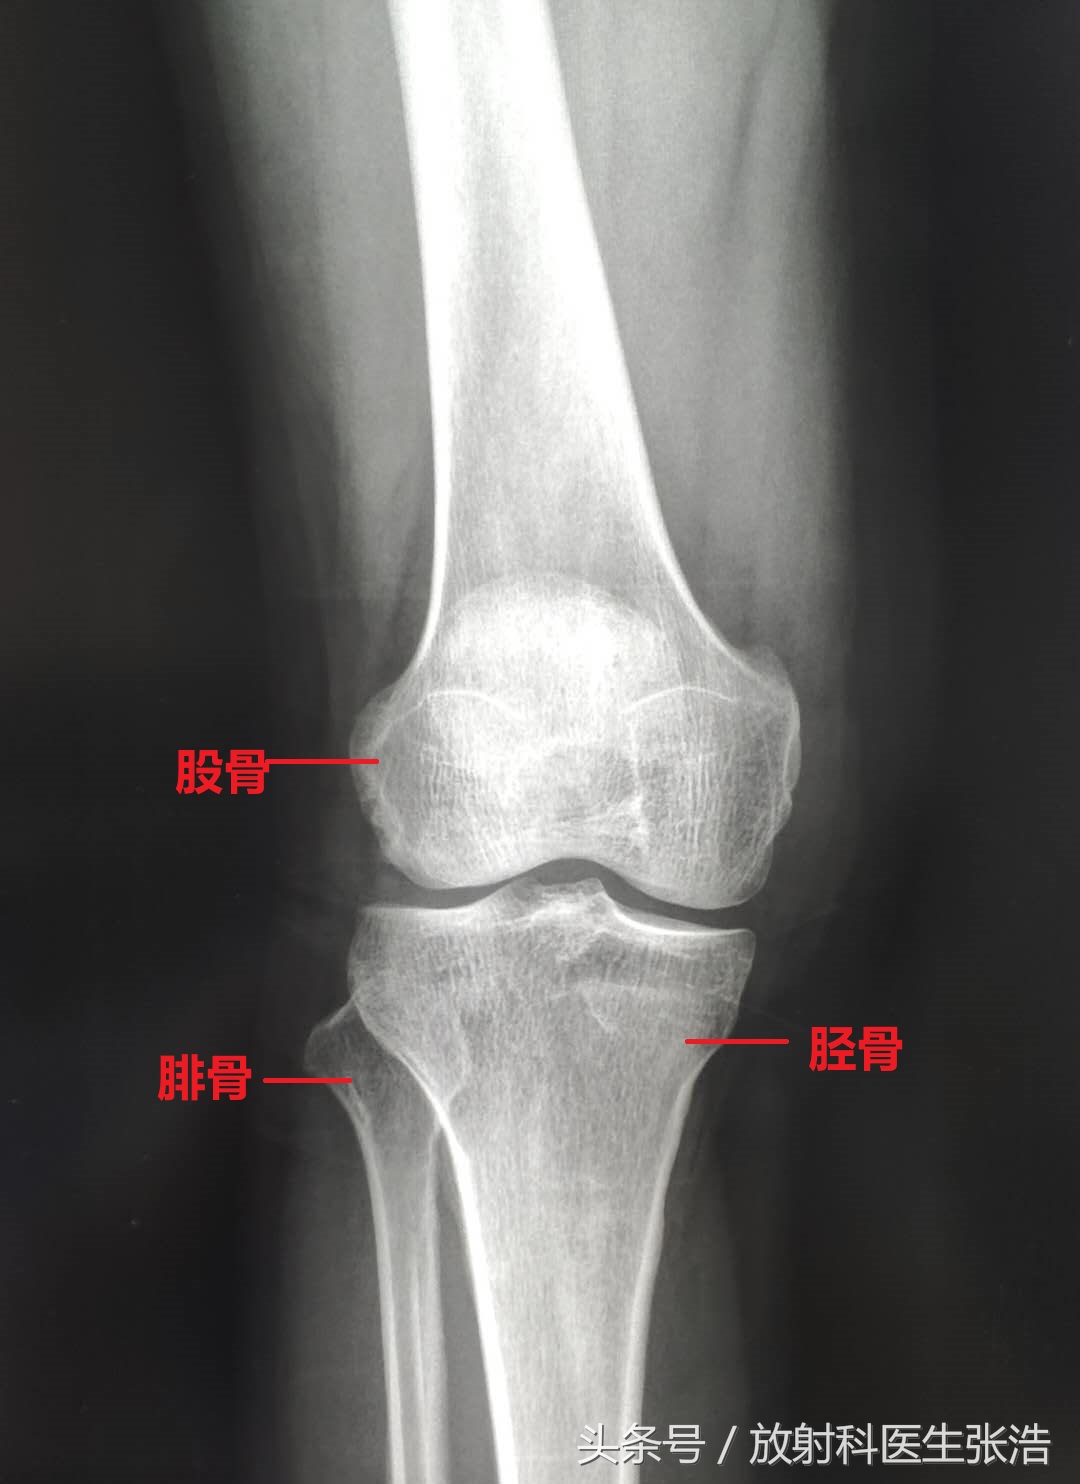

我们通常认为膝关节就是由几块骨头构成的(如上图所示),包括大腿的股骨,小腿的胫腓骨,还有前缘的髌骨,但是实际上膝关节的结构不仅仅有有这些结构,这些我们所熟知的只是膝关节的骨性结构,